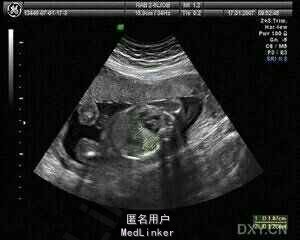

停经22周,发现羊水过多1周入院。23岁,G1P0,孕期规律产检,1周前产检发现羊水偏多,羊水指数25cm,今日复查b超,羊水量仍偏多,羊水指数为26cm,超声提示胎儿肺部发现一大约2*3肿物,考虑囊腺瘤样畸形。

入院完善相关检查:三大常规、肝肾功能、凝血功能未见明显异常,复查B超,仍提示囊腺瘤样畸形。

诊断:胎儿囊腺瘤样畸形。孕妇要求保胎治疗,请外科、麻醉科等多学科会诊,行CCAM经羊膜腔胸腔穿刺引流术。术程顺利,术后羊水量降至正常。孕35W时剖宫产1活婴,母婴平安。